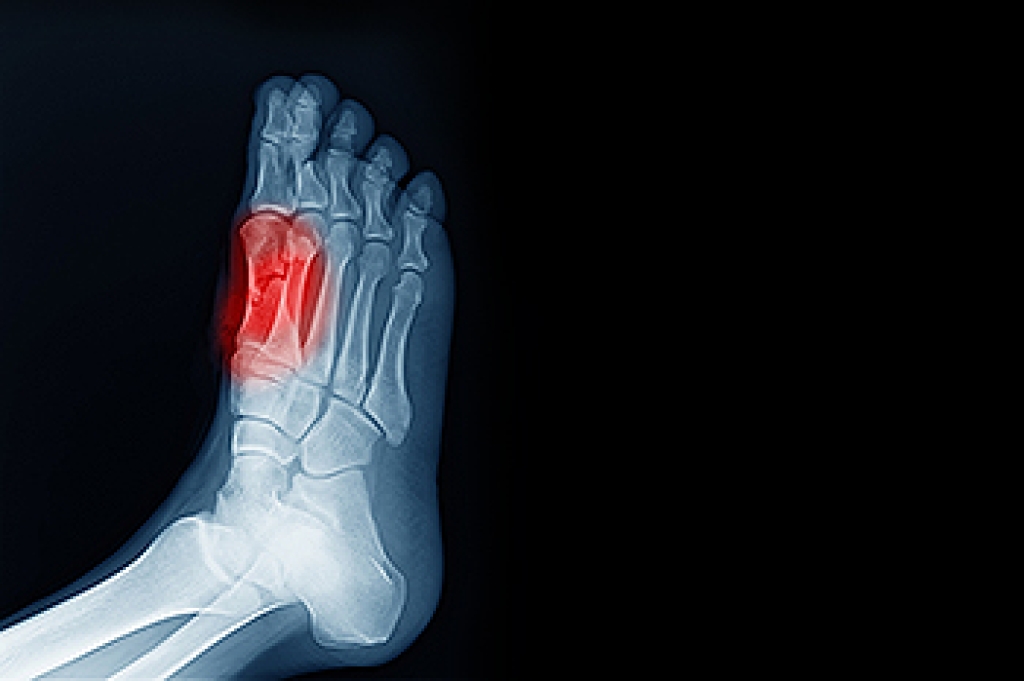

What are Causes of Congenital Foot Problem?

A congenital foot problem is one that happens to a child at birth. These conditions can be caused by a genetic predisposition, developmental or positional abnormalities during gestation, or with no known cause.

- Clubfoot, where tendons are shortened, bones are shaped differently, and the Achilles tendon is tight, causing the foot to point in and down. It is also possible for the soles of the feet to face each other.

- Vertical talus, where the talus bone forms in the wrong position causing other bones in the foot to line up improperly, the front of the foot to point up, and the bottom of the foot to stiffen, with no arch, and to curve out.

- Tarsal coalition, when there is an abnormal connection of two or more bones in the foot leading to severe, rigid flatfoot.